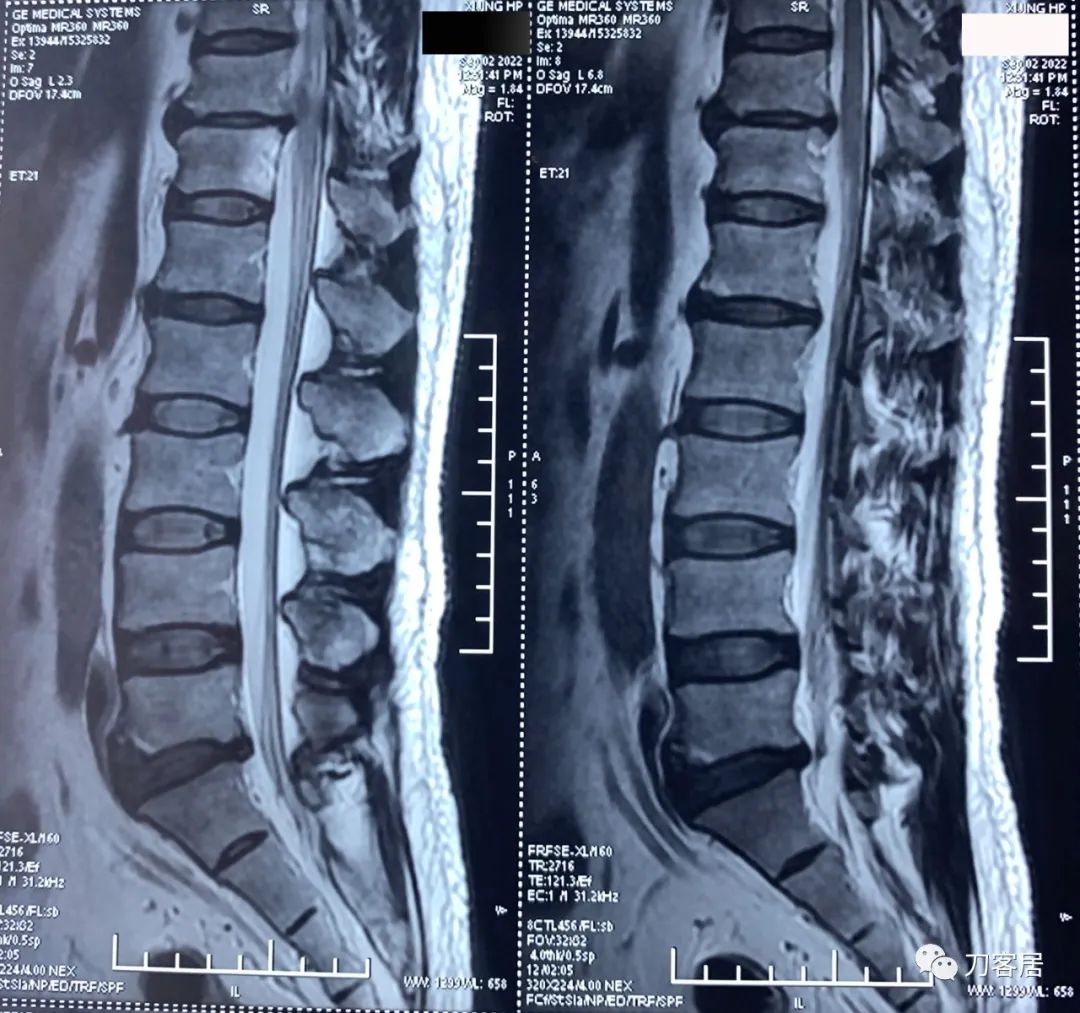

图23. 20220902西京医院腰椎MRI01,显示腰5骶1椎间盘突出,但不严重。

图24. 20220902西京医院腰椎MRI02,显示腰5骶1椎间盘突出,但不严重。

图25. 20220902西京医院腰椎MRI报告